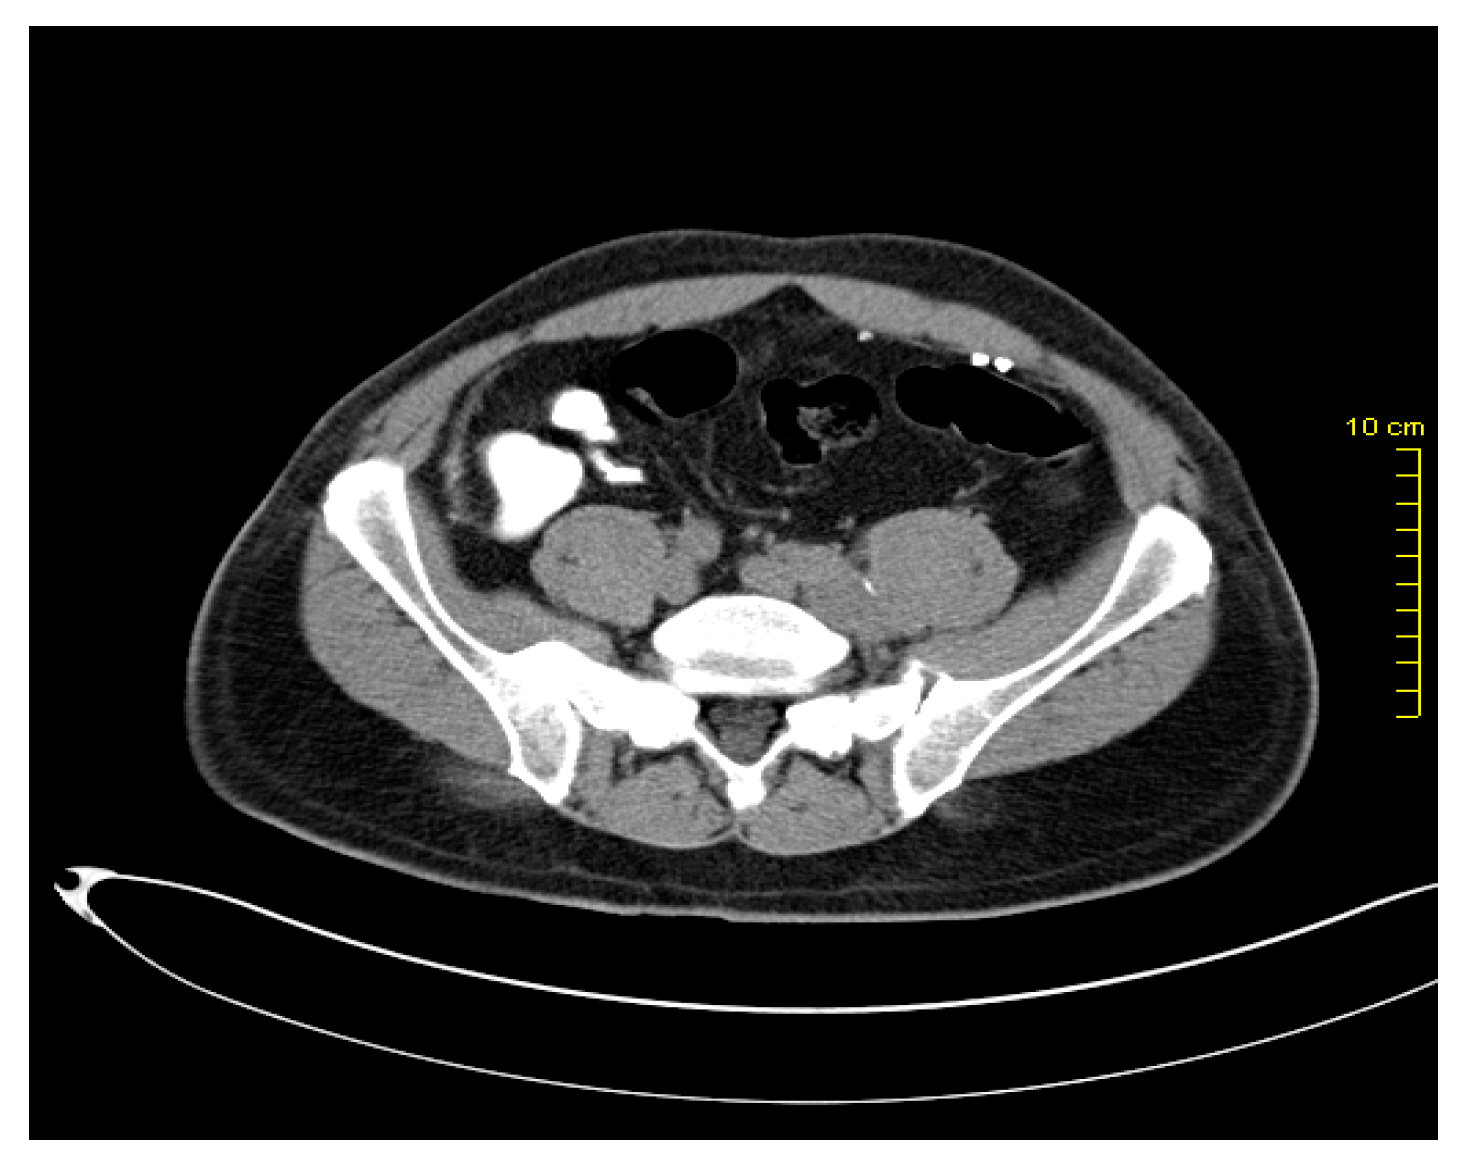

After two years, in March 2016, during the re-examination of the patient, pelvic lymphadenopathy was detected (Figure 1 and Figure 2), which, with the subsequent biopsy, was identified as disease progression with Vimentin(+), Melan C(+), S-100 (+), and AE1/AE3(-).

Figure 1. Pelvic lymph node metastases.